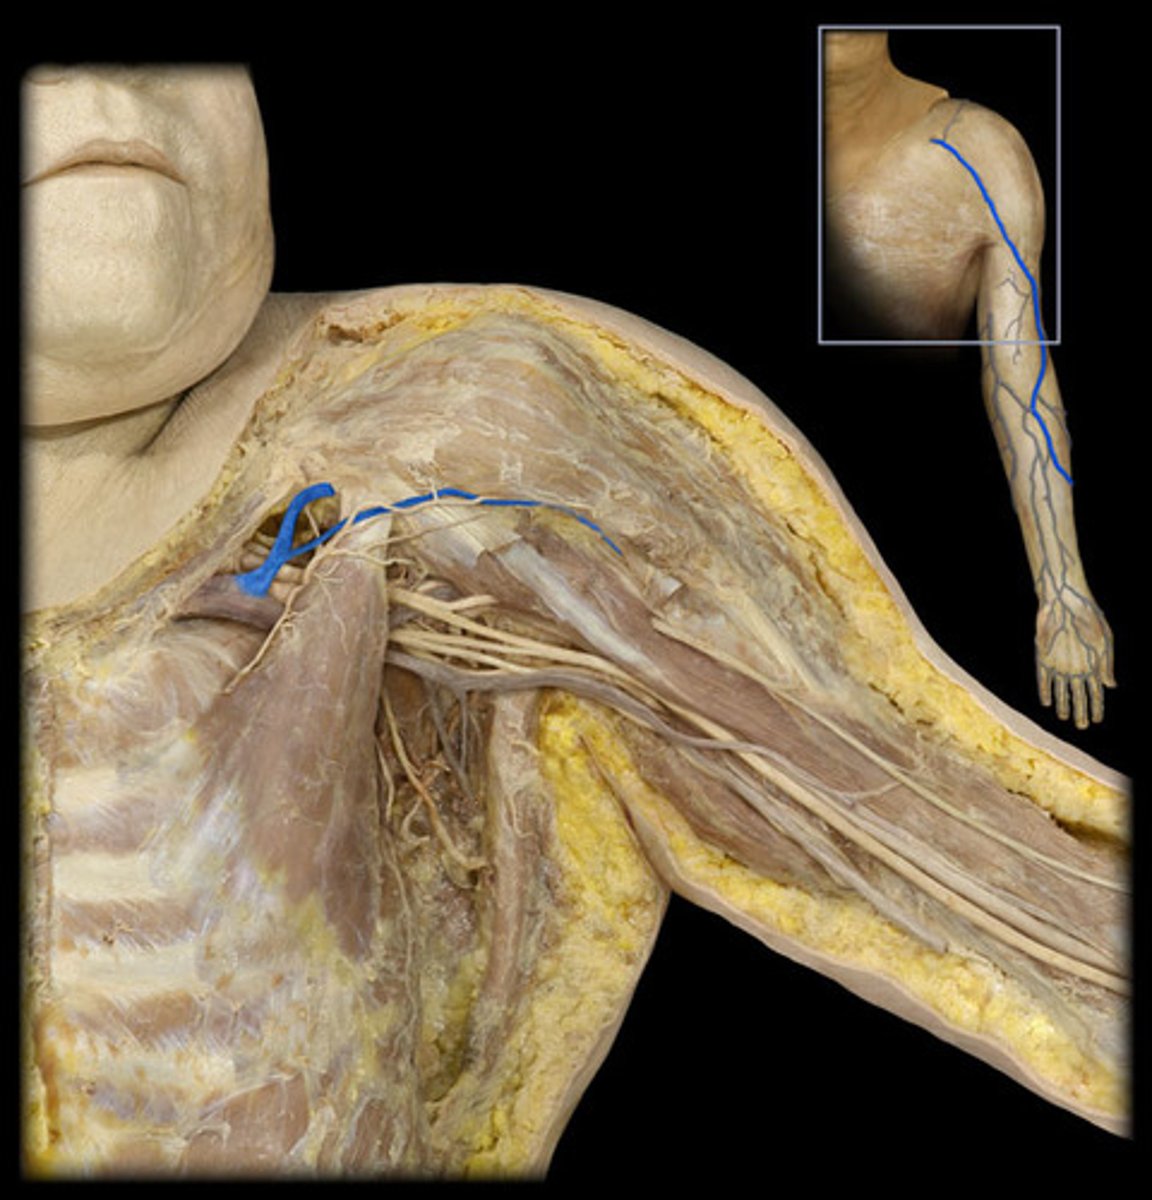

Axillary a.

armpit

Axillary v.

pertaining to the armpit

Axillary n.

pertaining to the armpit or underarm